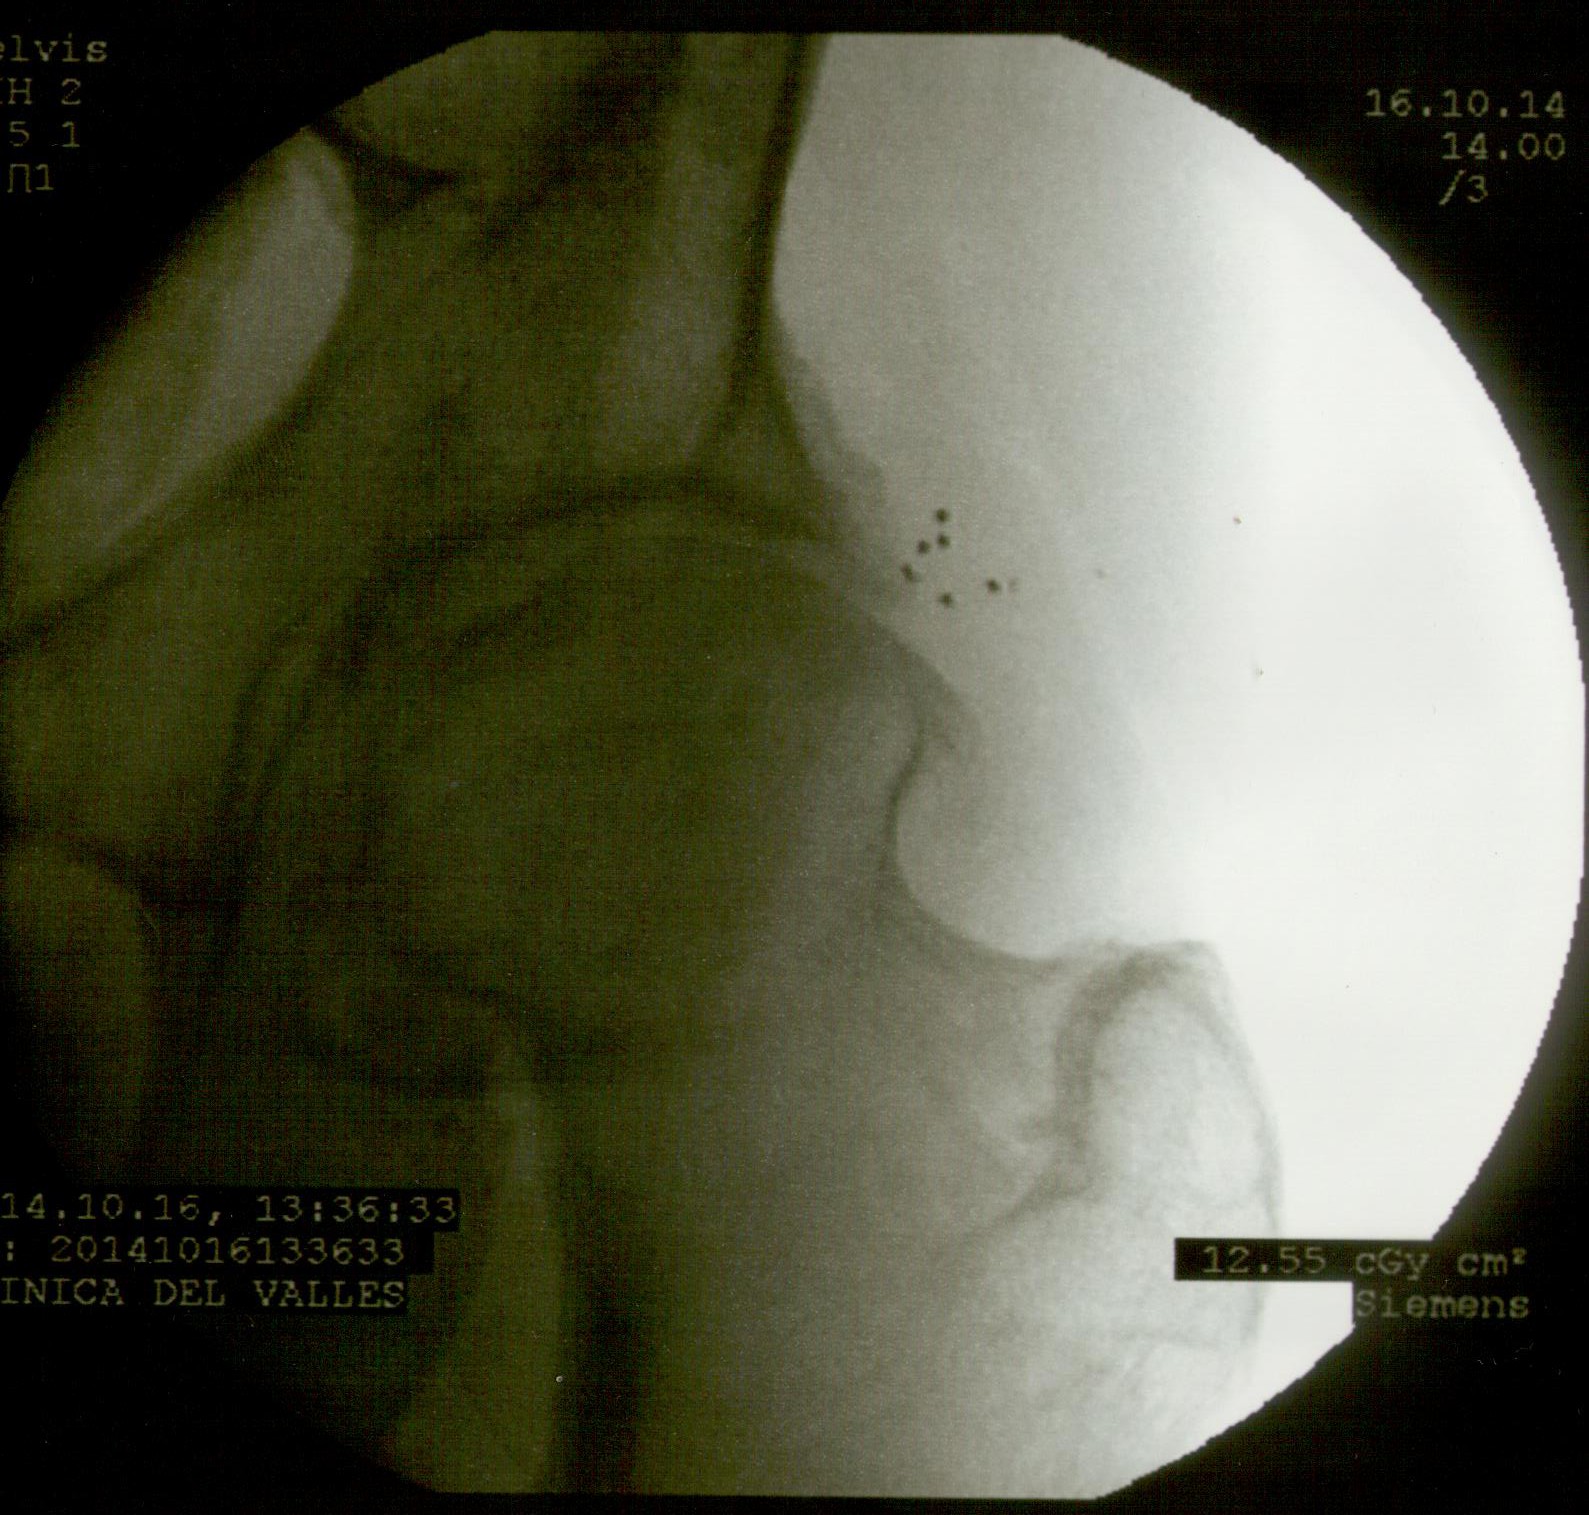

A continuación las imágenes de radioscopía que corresponden al paciente en cuestión. Se observan en primer lugar la colocación de las agujas que vehiculizan los microimplantes, y éstos (pequeños puntos) ubicados próximos a la ceja cotiloidea y a la osteofitosis de la cabeza del fémur.